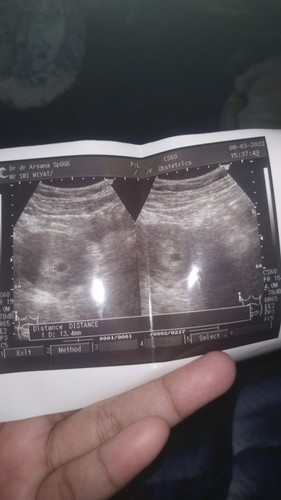

#seriusnanya #bantusharing #ingintahu #pleasehelp Mau tanya dong bund .. #seriusnanya hamil 7minggu kluar cairan coklat / flek apakah aman bunda ?😢 Awal kehamilan pun tidak merasakan mual muntah hanya merasa lelah dan punggu sering sakit #bantusharing Mohon bantuannya ya bunda #ingintahu #pleasehelp